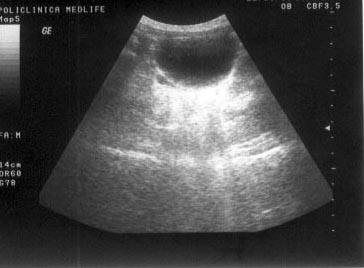

SEMIOLOGIE ECOGRAFICA

SEMIOLOGIE ECOGRAFICA Ecografia foloseste notiuni semiologice bine definite care incearca sa explice modificarile produse de traversarea ultrasunetelor prin tesuturi cu densitati diferite. Informatia ecograCiteste tot ... 2060 cuvinte